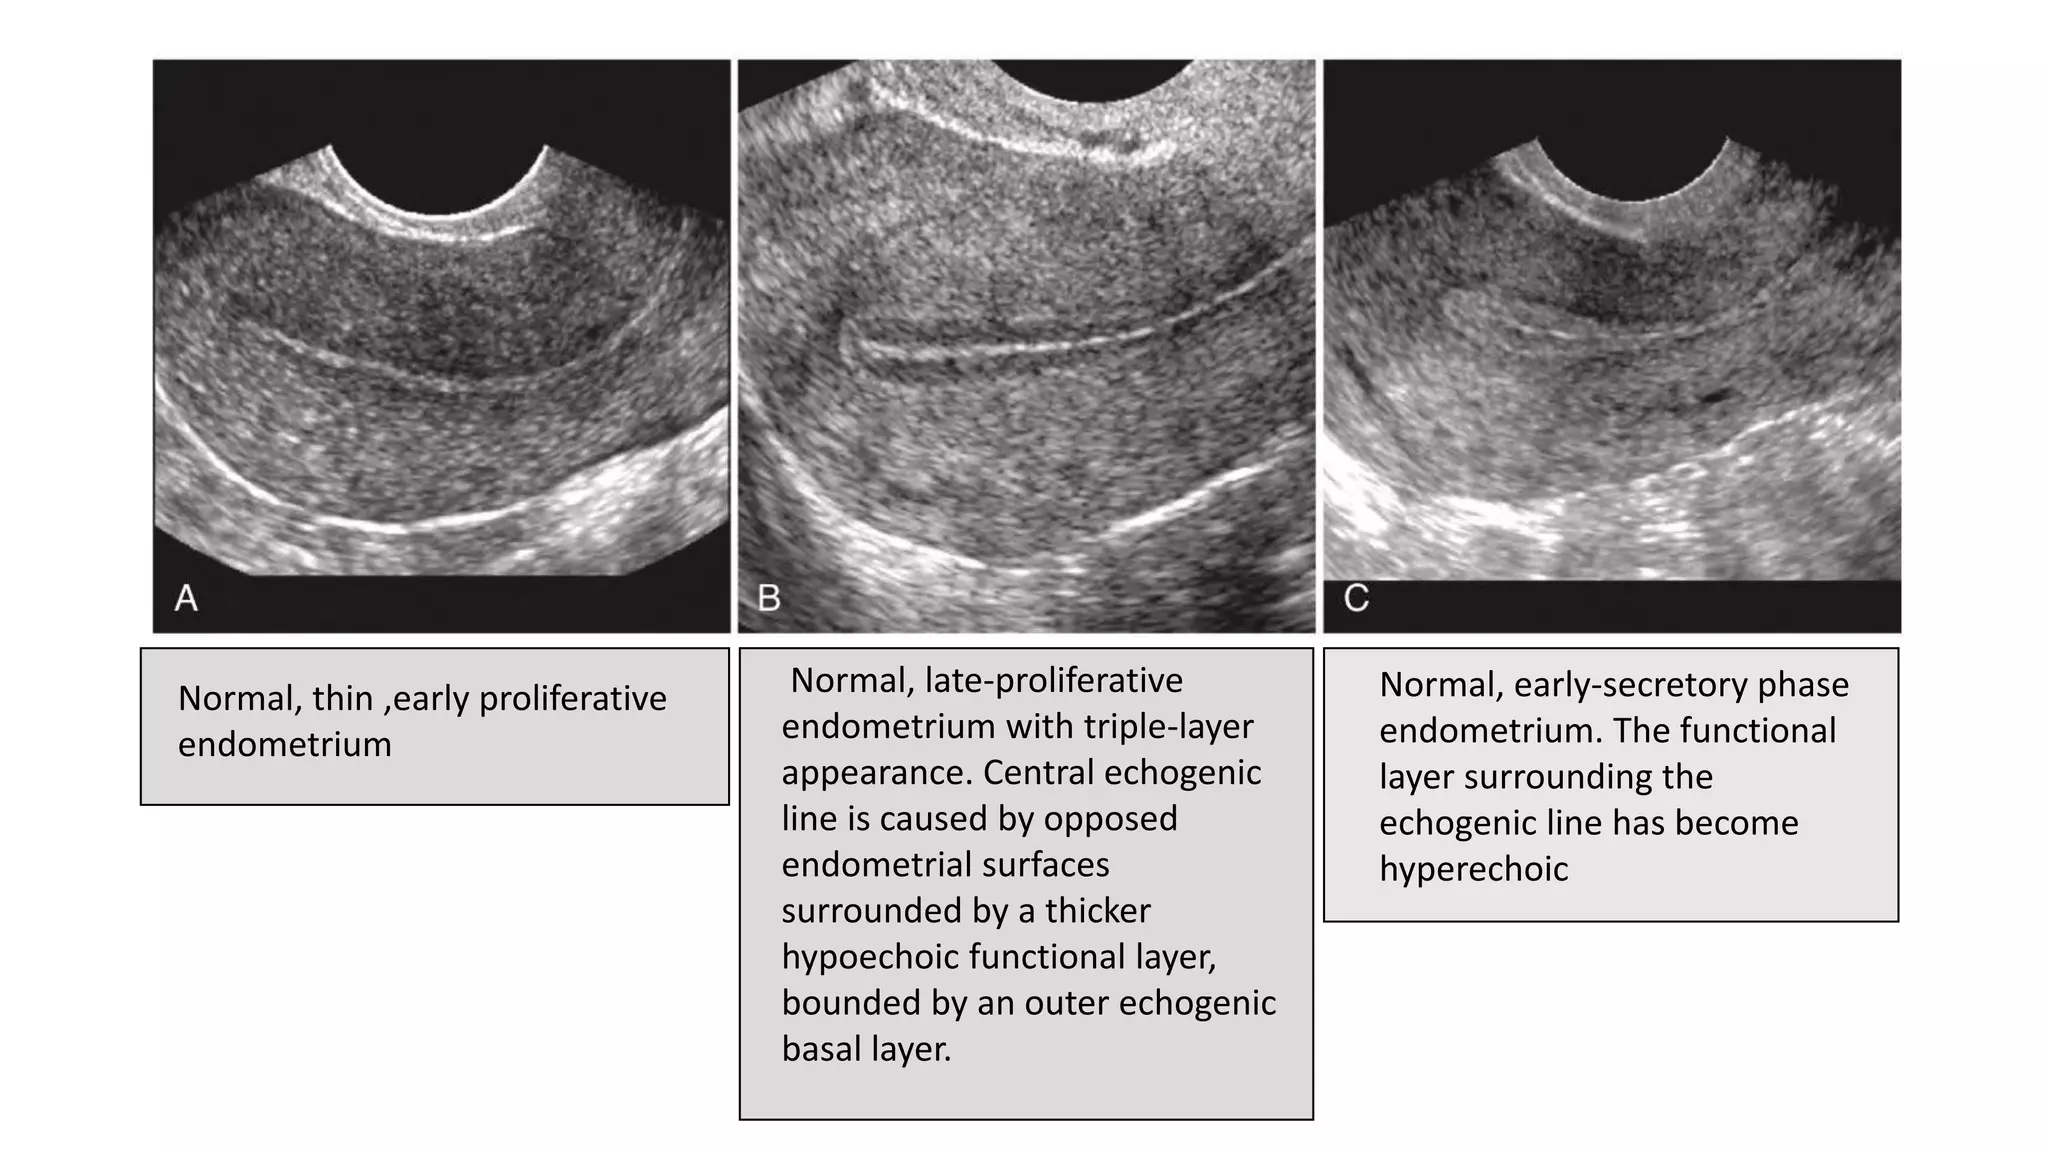

• The menstrual phase

endometrium consists of a

thin echogenic line.

• During the proliferative

phase, the endometrium

thickens, reaching 4 to 8 mm

• Periovulatory phase .

endometrium measures 6-

10mm and gives three layer

appearance

Normal, thin ,early proliferative

endometrium

Normal, late-proliferative

endometrium with triple-layer

appearance. Central echogenic

line is caused by opposed

endometrial surfaces

surrounded by a thicker

hypoechoic functional layer,

bounded by an outer echogenic

basal layer.

Normal, early-secretory phase

endometrium. The functional

layer surrounding the

echogenic line has become

hyperechoic

Normal, thick, hyperechoic late-secretory

• Secretory phase.

The endometrium in this

phase measures 7 to 14

mm in thickness.